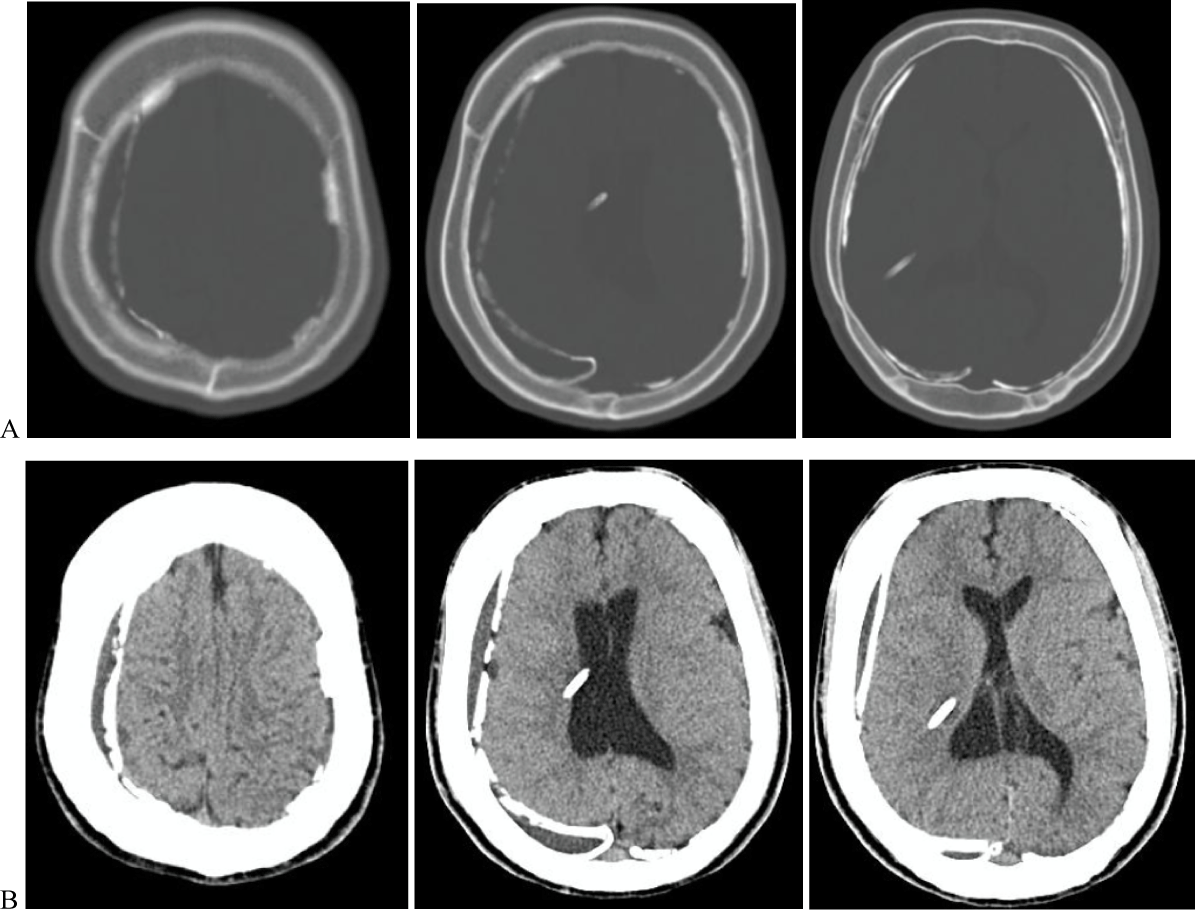

An urgent brain CT scan revealed bilateral calcified chronic subdural hematomas, consistent with the radiological appearance of an "armored brain." No other intracranial lesions were identified, and there was no evidence of ventricular dilation (Figure1).

Figure 1: Non-contrast head computed tomography, A-Bone and B-Brain windows on axial computed tomograph imaging of the head demonstrating billateral calcified chronic subdural hematomas, and a non-dilated ventricular system. View Figure 1